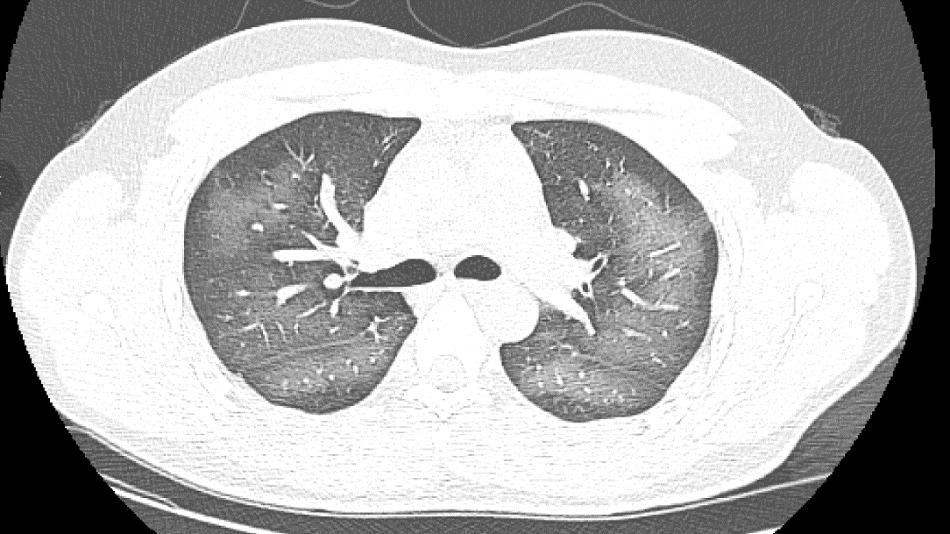

经检查,肺部 CT 片显示,李林双肺赫然呈现大范围白色样病变,报告提示 " 白肺 "。

长沙市第三医院放射影像科副主任、主任医师肖海清表示," 白肺 " 一般是指重症肺炎在 X 线或 CT 检查下的表现,患者肺部呈现一大片的白色状态。" 白肺 " 患者往往会出现呼吸困难、呼吸衰竭,严重者还会出现其它脏器功能障碍。" 白肺 " 常见于高龄(65 岁以上)、免疫力低下、有重要器官慢性病史(如心脏病、中风史、慢性肾脏病、慢性阻塞性肺疾病等)、有多种疾病并存(比如既有高血压、糖尿病,又有心脏病、肺病、肾功能不全)等人群。

长沙市第三医院放射影像科主任张秀萍表示,除了感染、弥漫性肺泡出血综合征等 " 白肺 " 最常见的病因外,吸入有害物质如粉尘、喷雾等,也可导致肺部出现大范围白色样病变。这位年轻的患者就是因为使用不当,吸入了一部分防晒产品进入肺部,导致 " 白肺 " 的发生。